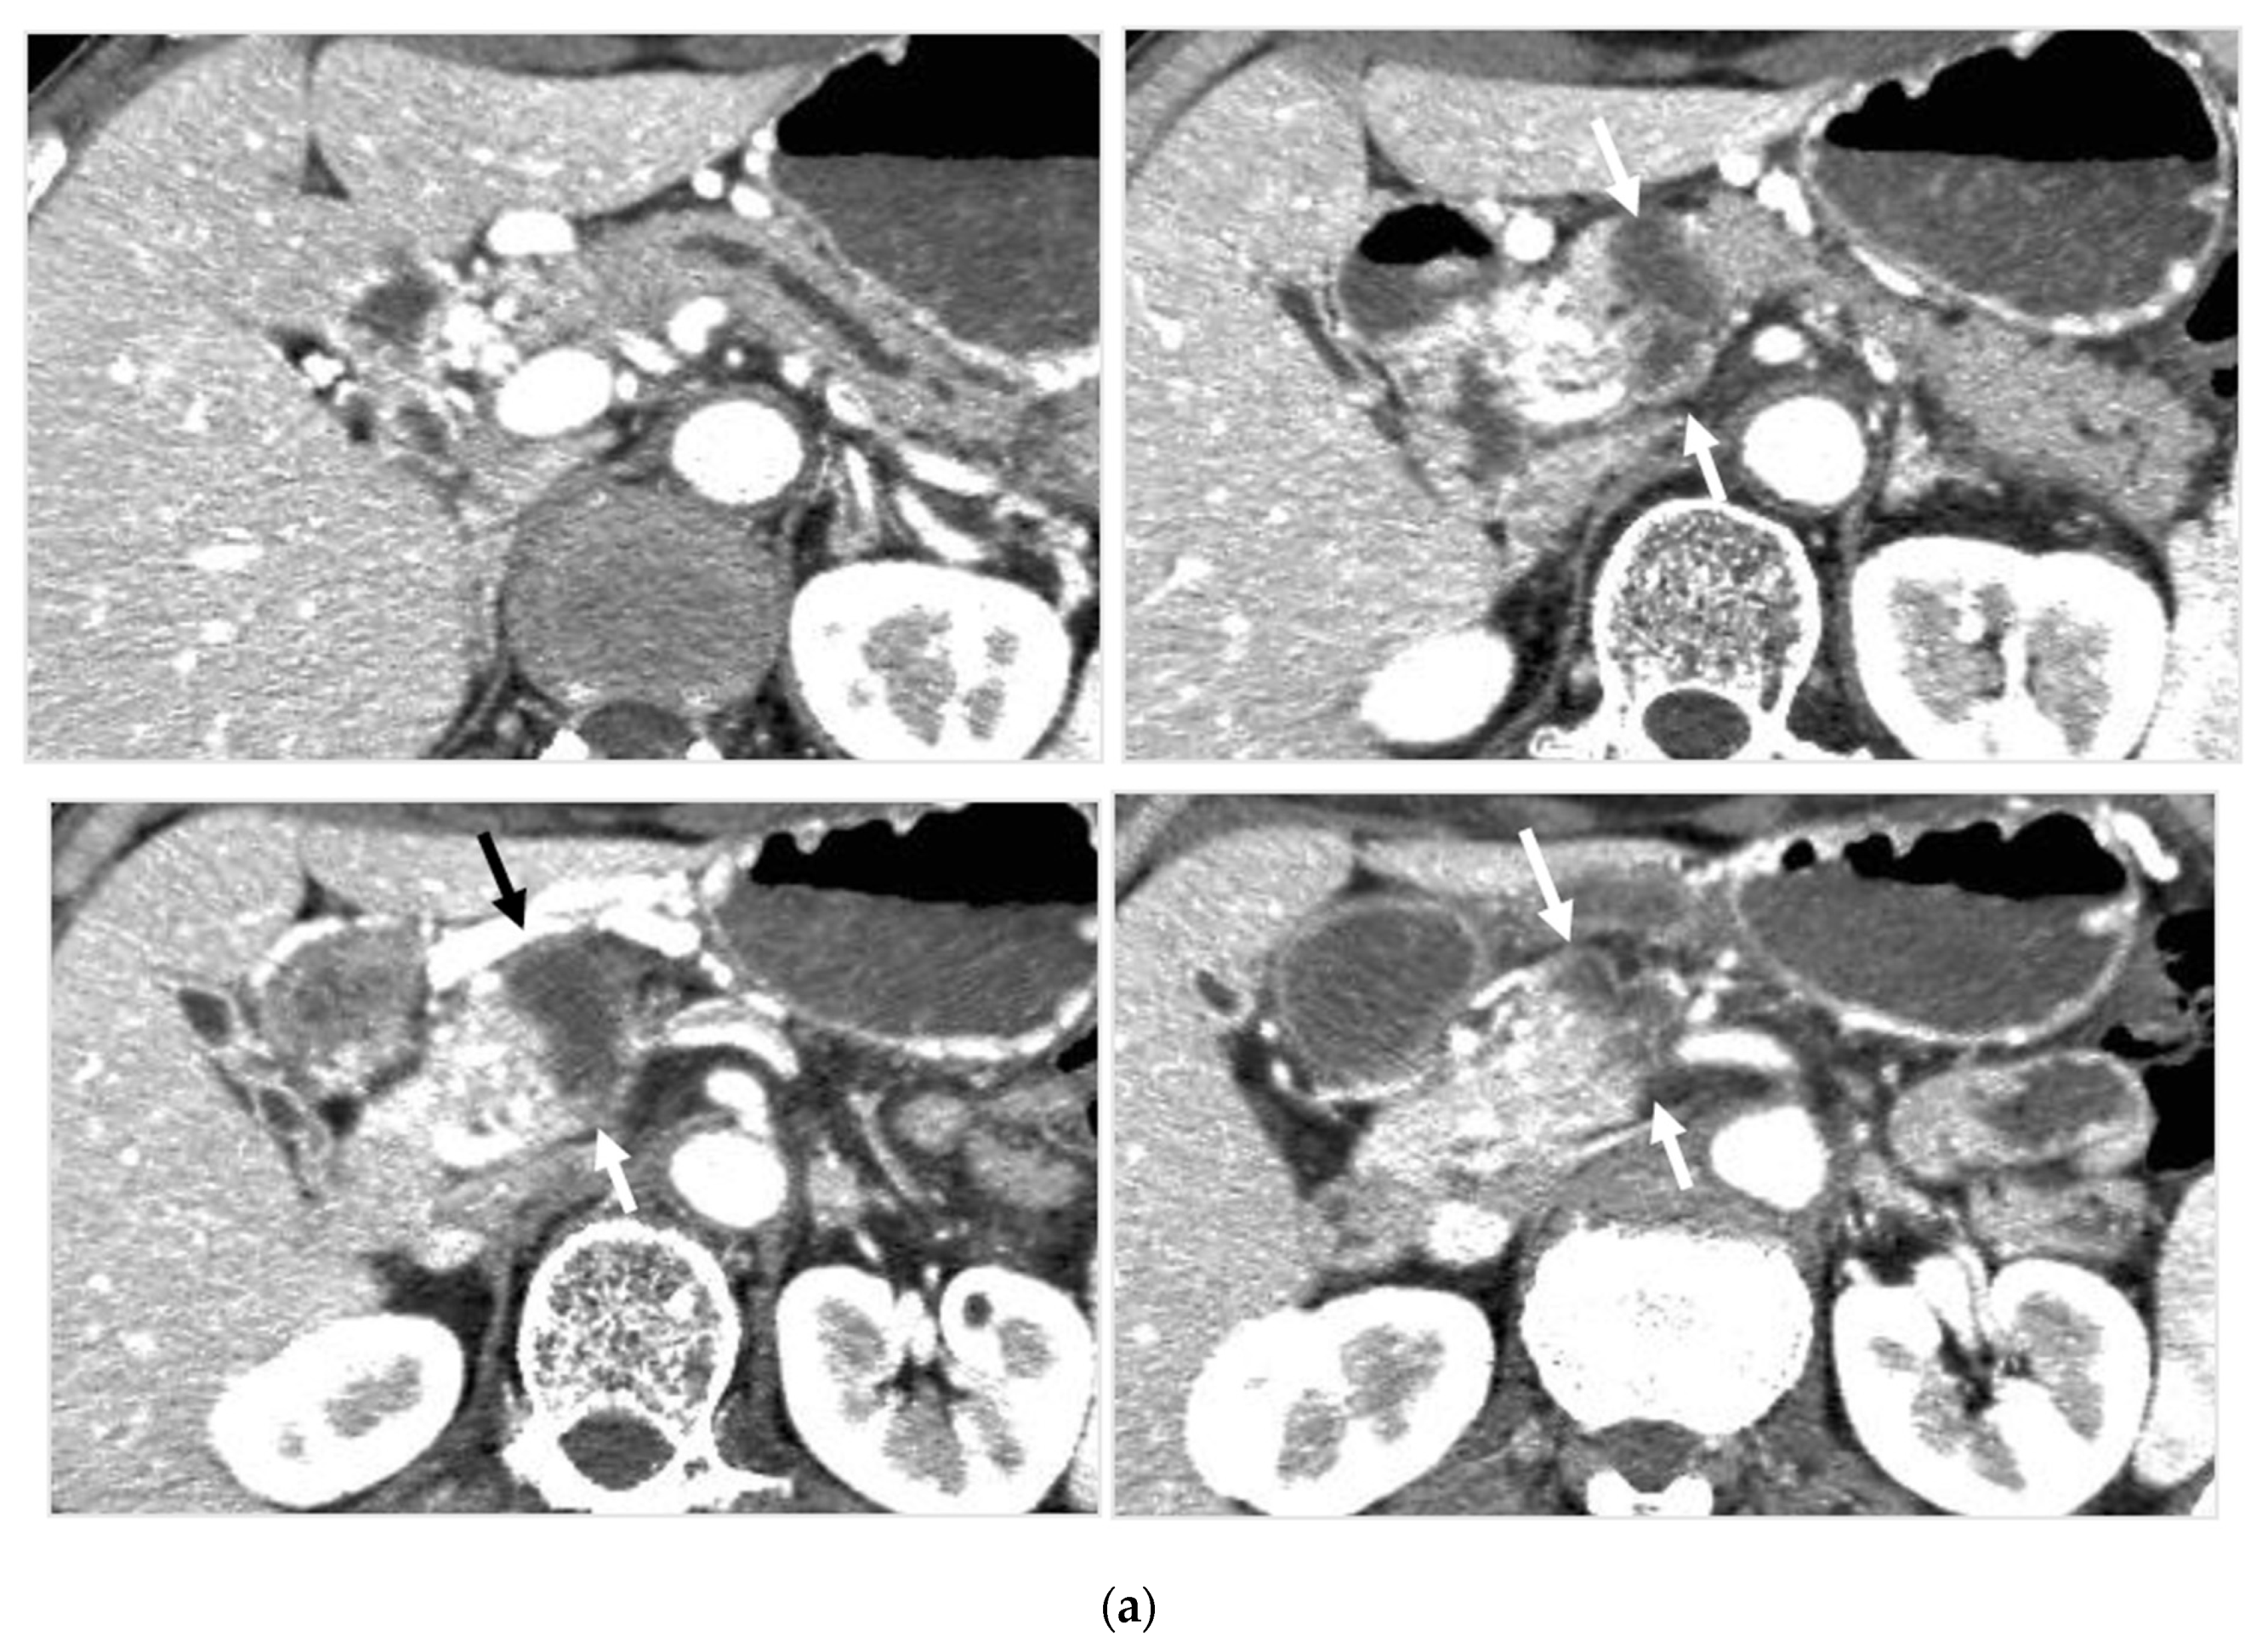

Identifying Supplying Arteries to Pancreatic Cancer

Method of Arterial Administration of Anticancer Agents

2.5.1. Judging Completeness or Incompleteness of Arterial Administration of Chemotherapeutic Agents